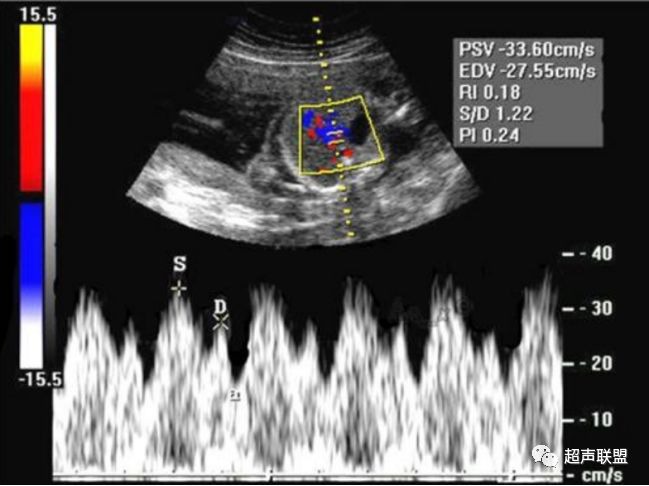

图2 脐动脉舒张期血流消失或反向

图3 正常大脑中动脉血流频谱